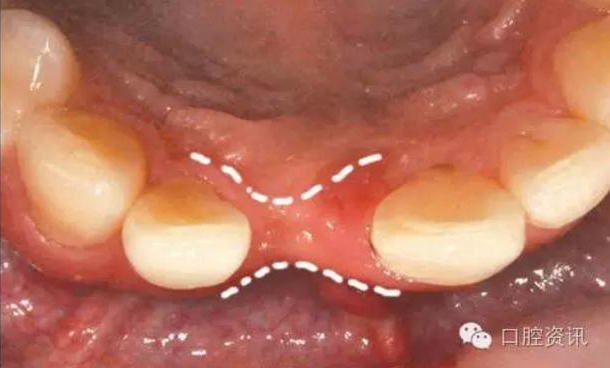

牙醫(yī)會根據(jù)您本身的條件重建和美化口腔。您本身的條件一般指植體

周圍骨和軟組織的質(zhì)、量。有一些軟組織不足( 例如, 牙齦缺損 ) 的病

例可能需要軟組織移植 ( 例如, 從上腭取一塊黏膜) 來獲得理想的美

觀效果, 有一些病例可能只有降低美觀要求才能達(dá)到更好的修復(fù)效

果, 這需要綜合考慮。